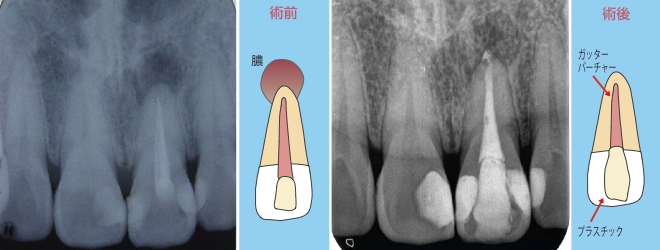

前歯の症例

- 3本に病変が見られ、それぞれに色々な問題があったので個々の歯に合わせたアプローチで治療を行いました。

- 歯と同じぐらいの大きさの病変が出来てしまっていました。健康な歯が多く残っていれば当院ではビルドアップ(http://www.eedental.jp/buildup.html)で治療を行います。